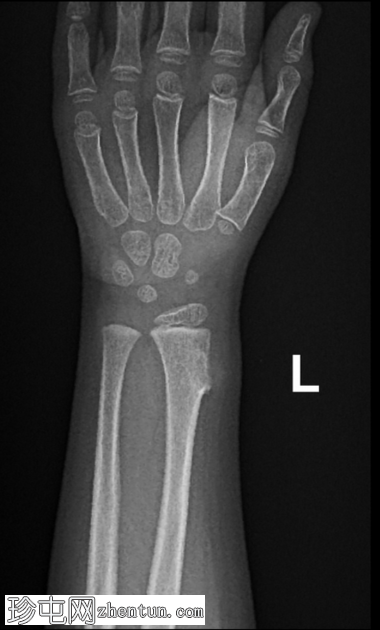

X线片

正位片

可见桡骨远端干骺端前外侧有一骨性增生。病变与母骨皮质和髓质相连。边界清晰。无皮质破损、骨膜反应及相关软组织肿块。邻近尺骨外观正常。无骨折或脱位。